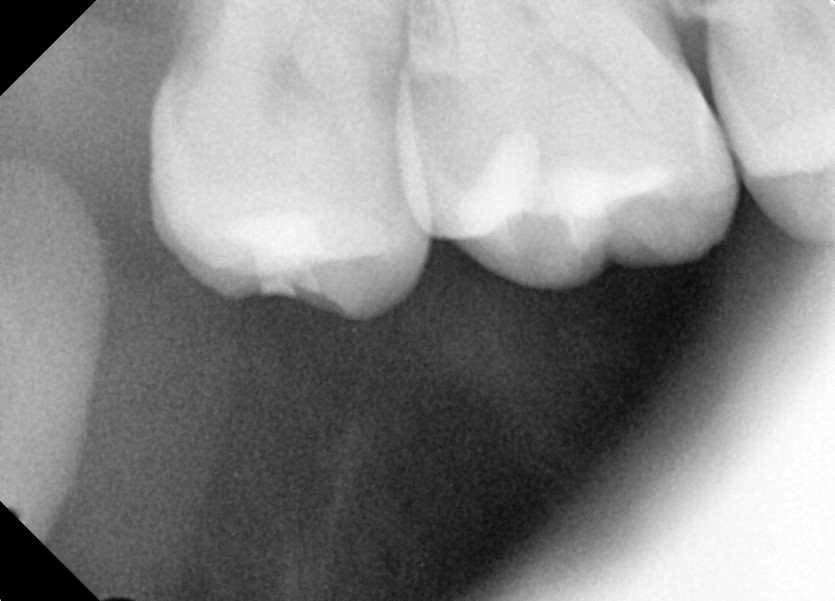

#18,48 사랑니 발치

구강 외과 전문의가 당일 발치했습니다.